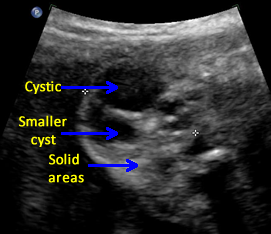

Above. Case 1. 24 3/7 weeks gestation. Sacrococcygeal teratoma. Longitudinal scan of lower spine showing sacrum with associated mixed cystic and solid mass.

Above. Case 1. 24 3/7 weeks gestation. Sacrococcygeal teratoma. An oblique scan through the same area shows both solid and cystic areas as well as calcifications, which are commonly seen in teratomas. The mass appeared completely external.

Above. Case 1. 24 3/7 weeks gestation. Sacrococcygeal teratoma. Similar part of the tumor as above showing cysts of various sizes.

Above. Case 1. 24 3/7 weeks gestation. Sacrococcygeal teratoma. The predominant cyst is large and contains anechoic fluid. No polyhydramnios or evidence for fetal hydrops were noted. Delivery occurred at term. Uneventful resection and repair occurred on day 2 of life.